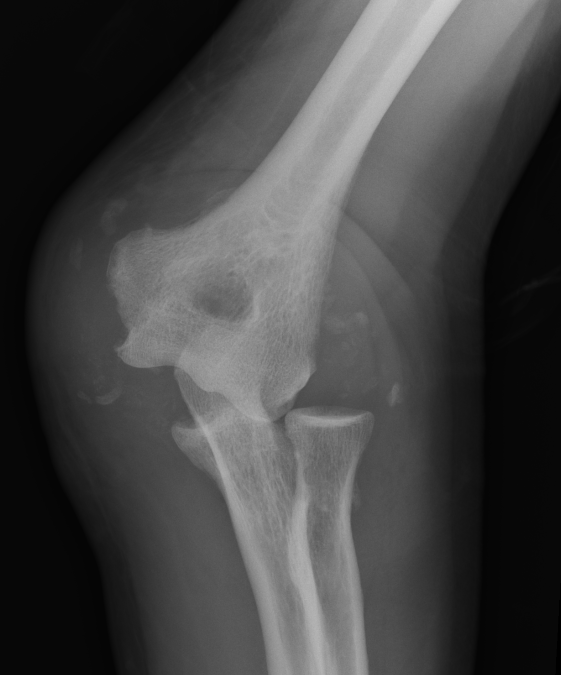

Surgical technique